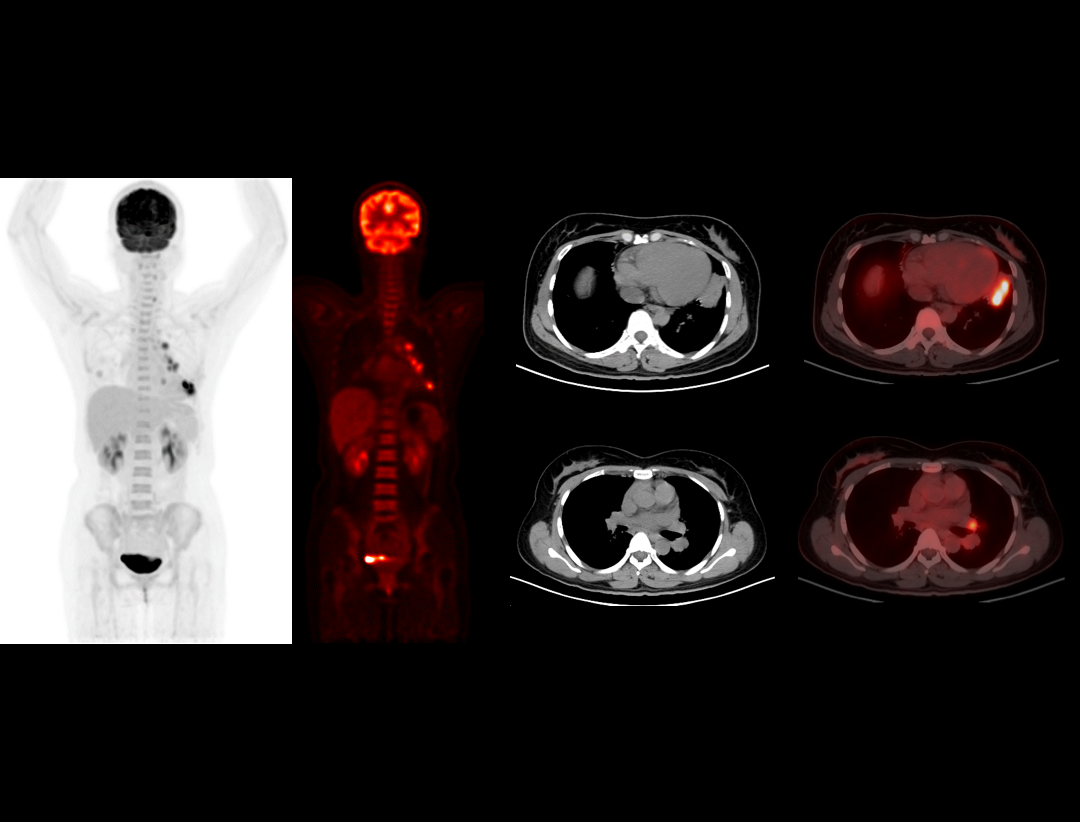

2.9mm

高いNEMA分解能。

TOF+PSF

分子イメージングの定義に革命を起こします。

600x600

画像の細部を可視化する高分解能イメージマトリクス。